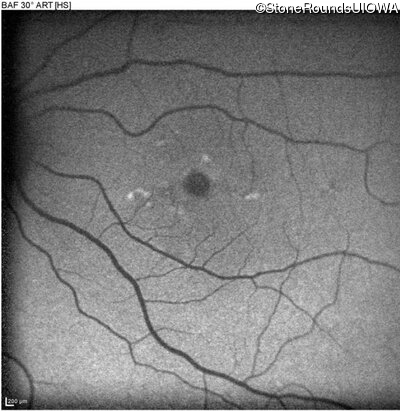

Blue Autofluorescence - Left - 20/63 -1

Exemplar

Blue Autofluorescence - Left - 20/50

Blue Autofluorescence - Left - 20/63